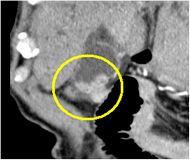

造影CT横断像(胆嚢がん)

造影CT冠状断像(胆嚢がん)

造影CT矢状断像(胆嚢がん)

無症状の方でも超音波検査、CT検査により偶然、胆嚢内に腫瘍が見つかることがあります。胆嚢の腫瘍では胆嚢ポリープや胆嚢腺筋症など、良性腫瘍が多く見られますが、中には胆嚢がんを認める場合があります。検査で胆嚢内の腫瘍を認めた場合には大きさや形状に応じて悪性腫瘍との鑑別が必要となります。